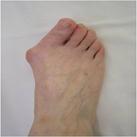

A bunion / Hallux Valgus is term for a boney bump that has formed on the inner aspect of the forefoot at the main big toe joint (Fig 1).

The medical term is hallux valgus, hallux being the latin name for the big toe, valgus describing the leaning of the big toe away from the midline of the body. This condition can run in families, presenting as early as adolescence or be acquired in later life (eg. as a result of footwear).